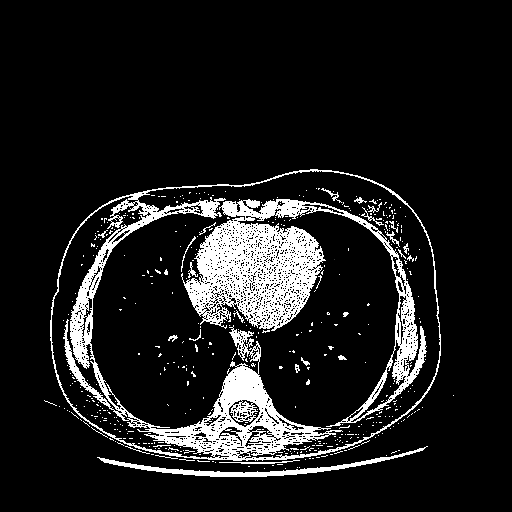

Generated VENOUS CT scan (A→B translation)

Full window (WL 1023.5, WW 4095 β†’ Low βˆ’1024, High +3071)

Actual HU range: [-1024.0, 3071.0]